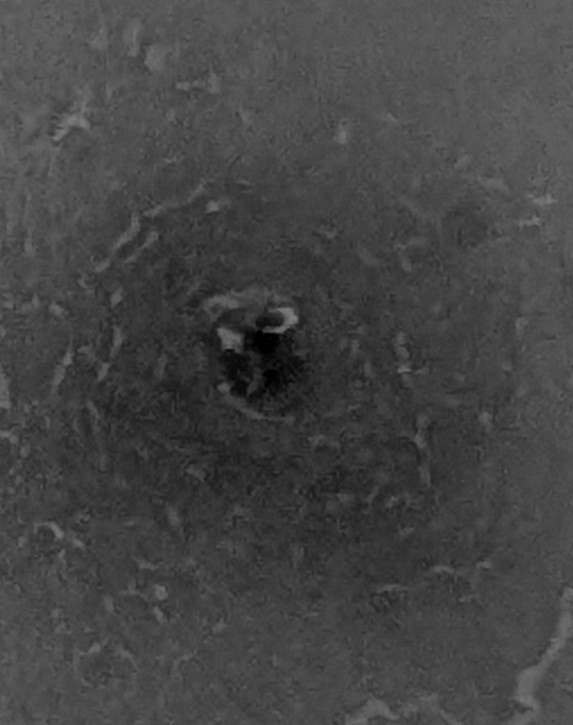

BCG를 맞았다. 주삿바늘로 피부를 살짝 떠서 결핵균을 몸속으로 들여보냈다. 별다른 느낌이 없던 찰나, 10초 뒤부터 왼쪽 어깨에 묵직한 통증이 밀려왔다. 신생아들 눈에도 눈물이 맺힌다며 접종실 직원이 고개를 끄덕였다. 진료실로 돌아와 나 역시 눈물을 찔끔 짜냈다. 이 아픈 BCG를 나는 왜 자처했을까.

며칠 뒤면 어깨에 고름이 차고 딱지가 앉을 것이다. 그러면 나는 40년 전 불주사를 맞았던 국민학교 이후 격동의 시대를 지나, 무사히 중년이 되었던 것처럼, 앞으로 10년, 15년은 거뜬히 버텨낼 수 있을 것이다. ‘하필 소아과 의사’였던 고단한 오늘을 기분 좋게 추억하면서 말이다.